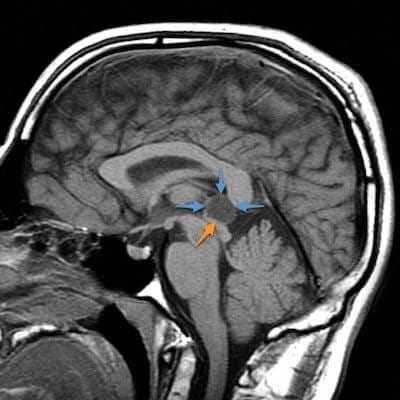

Подавляющее большинство кист шишковидной железы имеют малые размеры (в 80% случаев меньше 1 см) и характеризуются бессимптомным течением. Кисты, обуславливающие симптоматику, преимущественно возникают у женщин во второй половине жизни. Кисты большего размера могут обуславливать объемное воздействие на пластинку четверохолмия, приводя к сдавлению верхнего двухолмия и возникновению синдрома Парино. При сдавлении водопровода мозга, расположенным между третьим и четвертым желудочком, возможно развитие обструктивной гидроцефалии. Редко, в случае кровоизлияния в кисту, она может быстро увеличиваться в размерах. Это состояние называется апоплексией кисты шишковидного тела.

Киста шишковидной железы может обуславливать головную боль, нарушения зрения, невозможность перевести взгляд кверху или книзу. Редкие симптомы: атаксия, эмоциональные расстройства, нарушения мыслительной деятельности, головокружение, нарушения сна, тошнота, гормональный дисбаланс (раннее половое созревание, вторичный паркинсонизм).

Другие проявления, сопровождающие опухоль эпифиза, зависят от направления ее роста и распространения опухолевого процесса. Поражающее воздействие опухоли на ткани мозжечка обуславливает появление шаткости, двигательной дискоординации, мышечной гипотонии и тремора. Давление опухоли на верхние бугорки четверохолмия приводит к возникновению пареза взора кверху и конвергирующего нистагма (синдром Парино). Возможно косоглазие, двусторонний птоз, диплопия. В отдельных случаях манифестируют гипоталамические симптомы: анорексия или булемия, расстройство терморегуляции. Может наблюдаться несахарный диабет, ожирение, гиперсомния. Если опухоль эпифиза распространяется на турецкое седло, в клинике наблюдаются признаки, типичные для опухоли гипофиза.